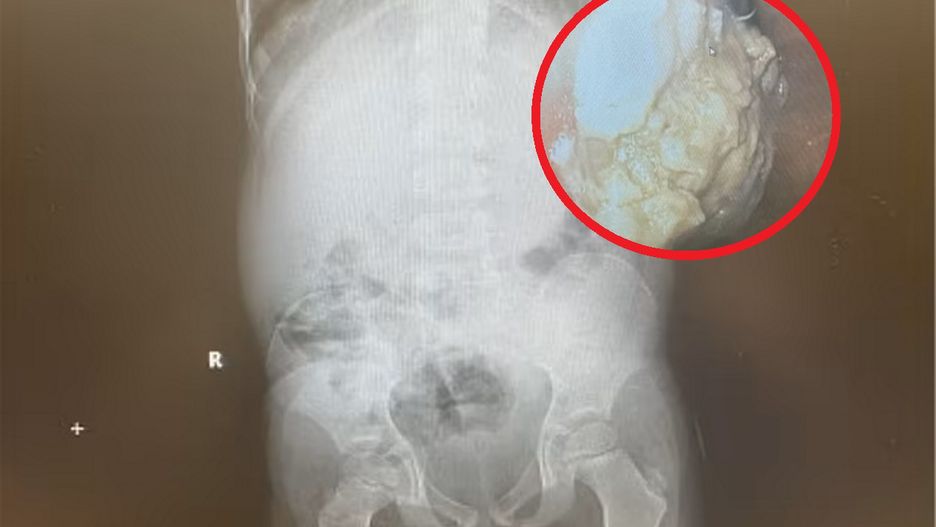

Bezoar w żołądku dziecka

Sytuacja, w której znalazł się chłopiec, była naprawdę niebezpieczna. Gumy do żucia zlepiły się w jego żołądku. Z czasem dziecko zaczęło odczuwać skurcze, miało też biegunkę. Akcja ratunkowa polegała na wyciągnięciu zlepionych gum z powrotem przez jego gardło.

Konglomeraty niestrawionych substancji, takich jak włosy czy właśnie gumy do żucia, formują się w zbite struktury. Nazywamy je wówczas bezoarami. Bywa, że ich obecność w układzie pokarmowym przez dłuższy czas pozostaje bezobjawowa. Mogą jednak powodować nudności, wymioty, bóle brzucha czy uczucie wczesnej pełności w czasie posiłku.